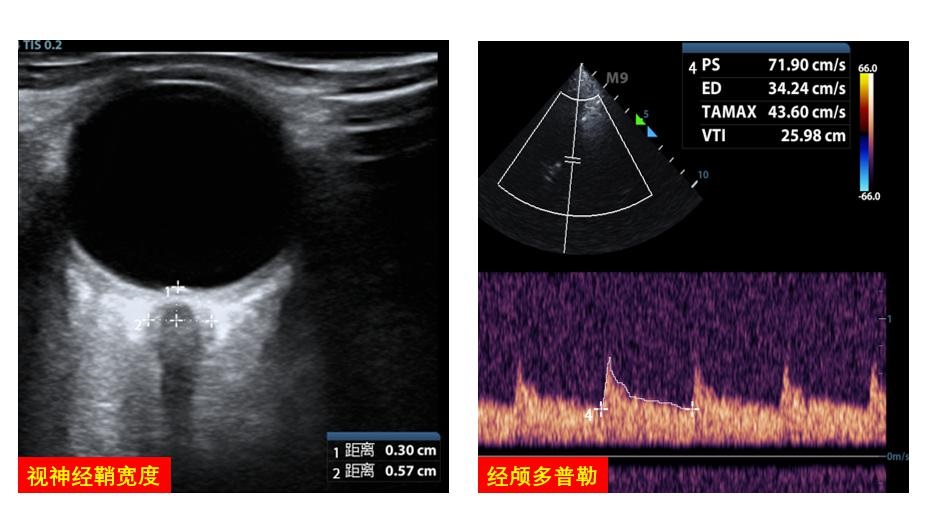

2.5 中枢神经系统大脑中动脉血流多普勒可协助评估脑血流灌注,协助调整VA-ECMO流量。视神经鞘宽度的超声探查可协助评估和管理患者脑水肿情况(图 21)。

| 图 21 中枢神经系统 |

目前一些床旁超声设备内预设了多种自动测量技术和算法,如自动LVOT VTI变异率、自动IVC定量分析等(图 31),为临床快速获得数据提供了便利,需要强调的是准确的计算结果依赖于清晰的成像和标准的位置及角度设置校正,其适用人群需要个体化判断。

| 图 31 自动计算工具 |